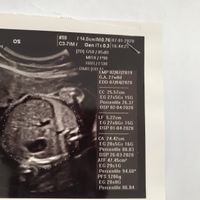

Buongiorno a tutte! Ho scoperto venerdì il mio positivo...oggi sono a 4+4 e la mia dpp è il 3 aprile 2020. Mi sa che sono la prima! Sono emozionatissima! Adesso aspetto con ansia il 20 agosto per fare...

Mi sa che sono la prima!!! la mia dpp è 5 marzo.... oggi sono a 4+5 .... ho qualche crampetto basso ventre ogni tanto.... poca fame ( cosa strana per me visto che di solito mangio anche i piedi del...